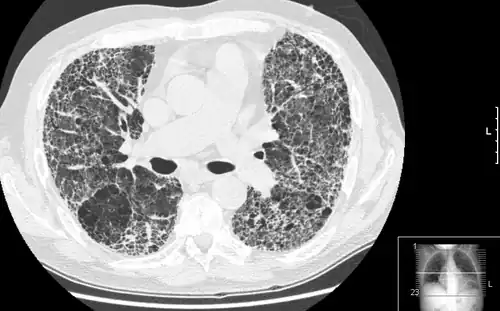

Pulmonary fibrosis is suggested by a history of progressive shortness of breath (dyspnea) with exertion. Sometimes fine inspiratory crackles can be heard at the lung bases on auscultation. A chest X-ray may not be abnormal, but high-resolution CT will often show abnormalities.[3]

Diagnosis

The diagnosis can be confirmed by lung biopsy.[3] A video-assisted thoracoscopic surgery (VATS) under general anesthesia may be needed to obtain enough tissue to make an accurate diagnosis. This kind of biopsy involves placement of several tubes through the chest wall, one of which is used to cut off a piece of lung for evaluation. The removed tissue is examined histopathologically by microscopy to confirm the presence and pattern of fibrosis as well as other features that may indicate a specific cause, such as specific types of mineral dust or possible response to therapy, e.g. a pattern of so-called non-specific interstitial fibrosis.